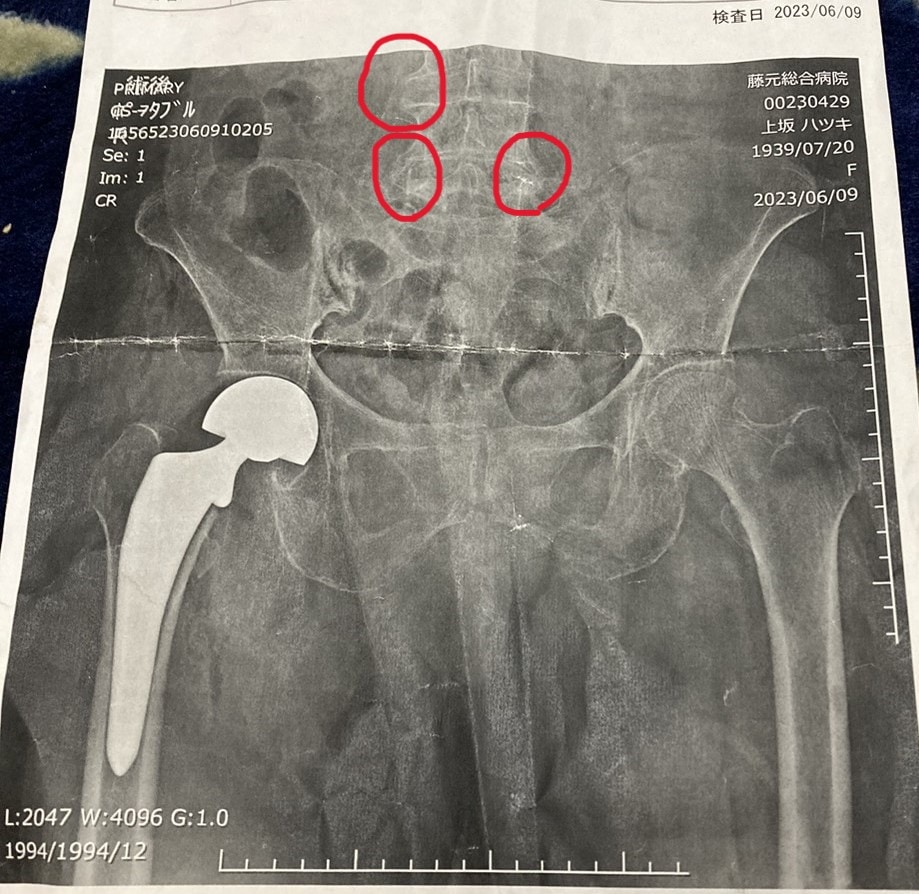

違う病院で、レントゲンを撮ると骨折。

その時の画像で、人工関節に置き換える判断をされたらしい。

(上は、自宅にあった紙焼きのレントゲンデータです。)

ただ、心配なのは、レントゲン画像をよく見ると

赤丸をつけたところに骨棘ができている事。

骨棘は、骨粗しょう症だとできやすいのだけれど、

折角、人工股関節に替えても、

人工骨を大腿骨に突き刺すようにして、

今はしっかり、固定されているけれど

大腿骨の骨密度が下がって、

人工骨が揺らぐようになったら困ります。

このことは、叔母さんの娘(つまり、私のいとこ)に

伝えてきました。